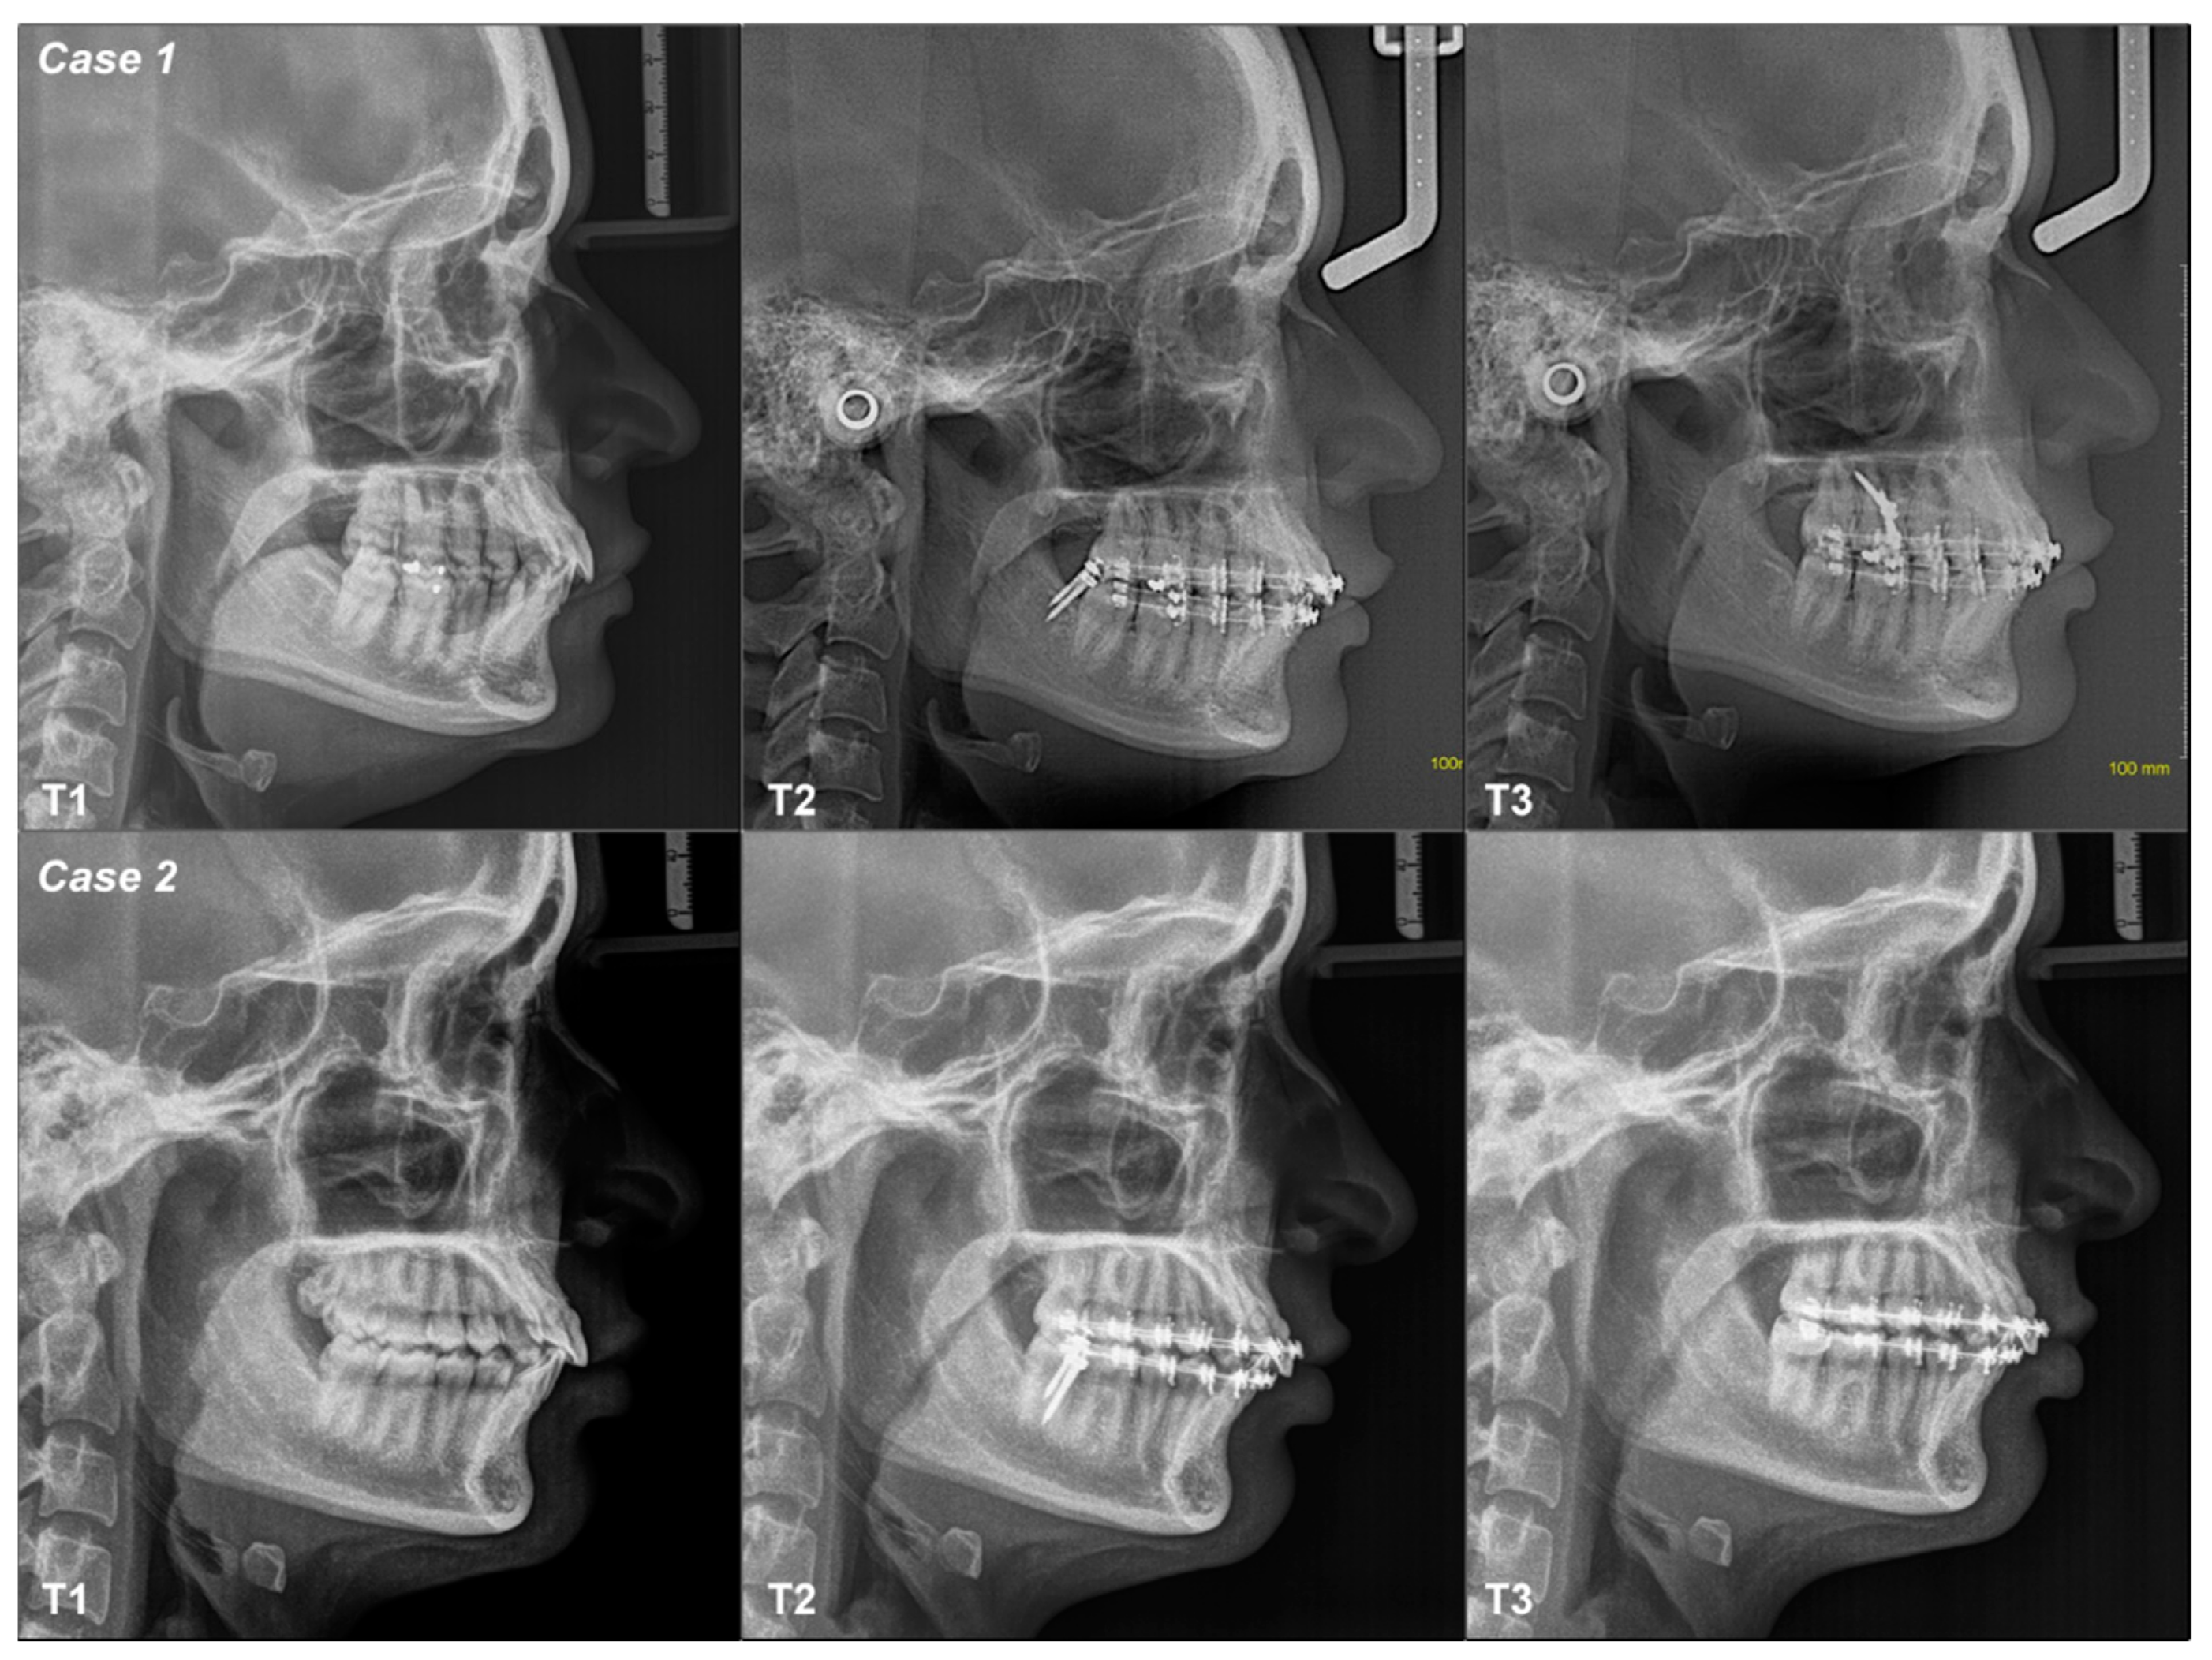

3.2.1. Case 1

3.2.2. Case 2